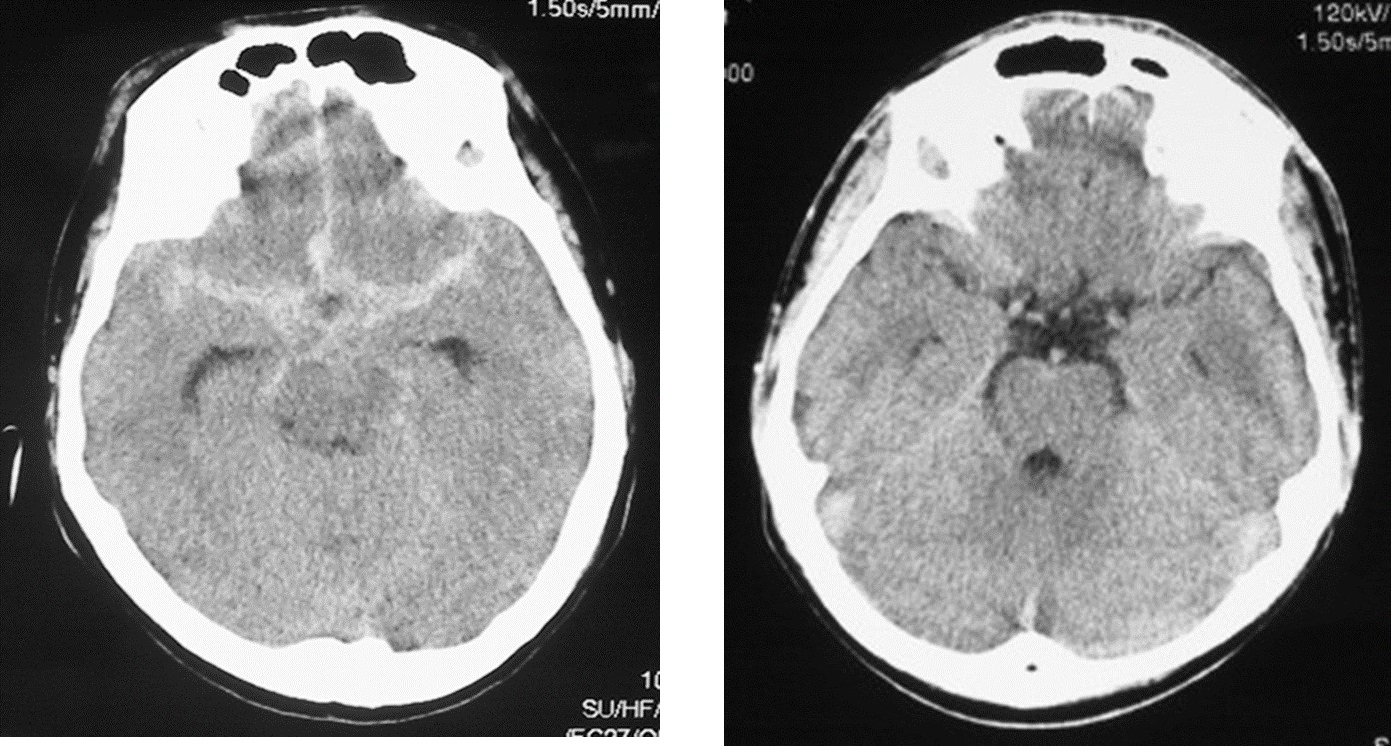

図:くも膜下出血のCT画像(左)と正常のCT画像(右)